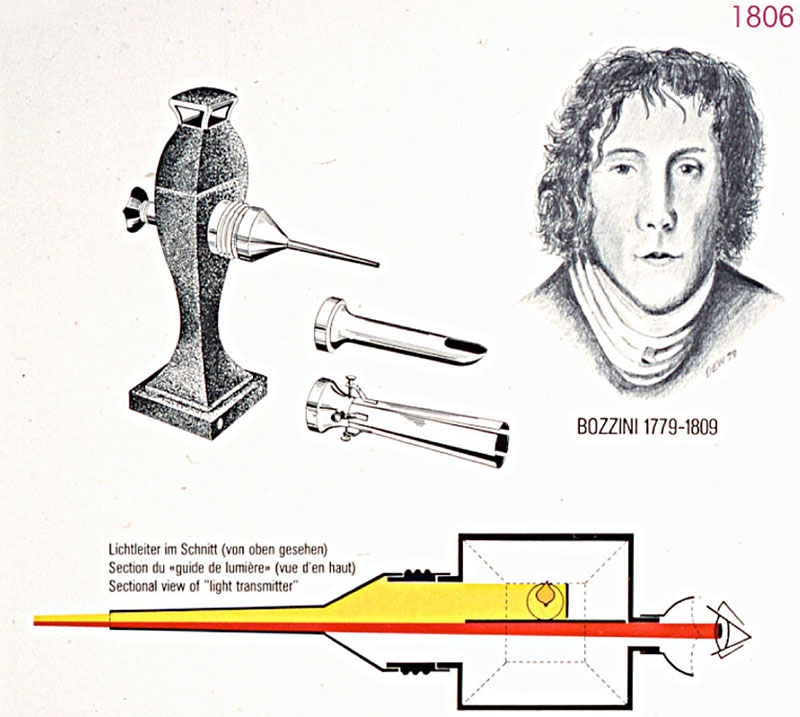

Endoskopinin Tarihi:

Endoskop ile insanların içine bakma merakı Mısırlılara kadar gider. Modern anlamda endoskoplar 18. Yüzyılda ortaya çıktı. Endoskoplar bugünkü incecik halini almadan önce eğilmeyen ve kalın çelikten yapılara sahiptiler. İlk endoskopi bir kılıç yutucusunda gerçekleştirildi.

NASA uzay teknolojileri sayesinde, fiberoptiklerin gelişmesiyle endoskoplar inceldi ve esnek hale geldi. Kliniğimizde kullanılan endoskoplar 5-7 mm inceliğindedir.